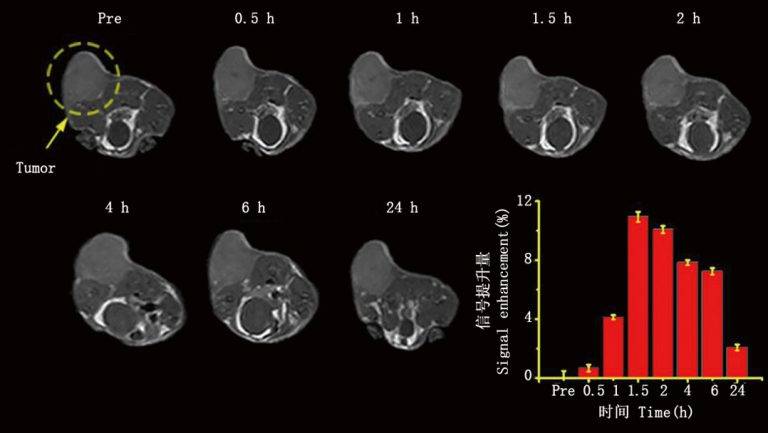

皮下腫瘤成像